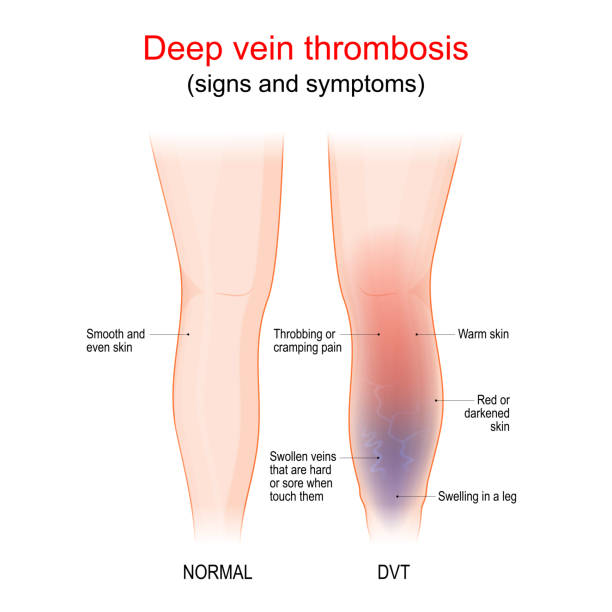

血栓性静脈炎とはの説明スライド - 医療のイラスト・写真・動画、素材販売サイトのメディック medick。

レバウェル看護 公式on X: "DVT 深部静脈血栓症 は理解できてる? @hayao_kamに可愛いイラストで分かりやすくまとめてもらいました。DVTの徴候や予防のための看護を確認しよう!🔽最後に看護クイズもあるよ! https:t.co dIdPk2Q2ed https:t.co hdDVZ7XoC6。

上皇后さまが発症された深部静脈血栓症について解説します下肢静脈瘤の原因・症状・治療方法・予防方法などを専門医が解説。

深部静脈血栓症 DVT の病態と予防見て!わかる!病態生理と看護 花子のまとめノート。

静脈血栓塞栓症ではどのような症状がありますか? 静脈血栓塞栓症。